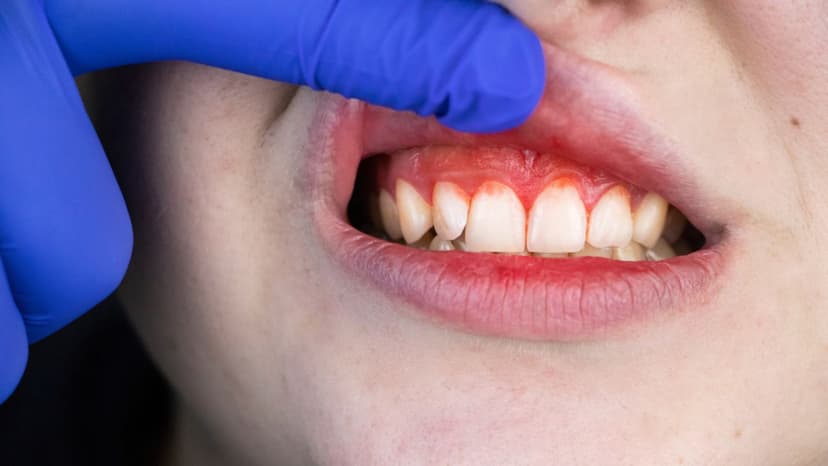

– Sưng nướu hoặc mủ quanh răng: Biểu hiện viêm nhiễm do vi khuẩn lan rộng ra vùng mô quanh răng.

Khi vi khuẩn sâu răng tấn công lớp ngà và men răng mà không được điều trị kịp thời, chúng sẽ tiếp tục xâm nhập sâu vào tủy – nơi tập trung nhiều dây thần kinh và mạch máu quan trọng. Hậu quả là người bệnh có thể bị viêm tủy răng, gây ra những cơn đau nhức dữ dội, đặc biệt vào ban đêm hoặc khi ăn uống đồ nóng, lạnh. Một số dấu hiệu nhận biết viêm tủy do đau sâu răng bao gồm: đau răng kéo dài và dữ dội, răng trở nên nhạy cảm hơn với nhiệt độ, vùng nướu quanh răng có thể sưng nhẹ, thậm chí xuất hiện triệu chứng sốt nhẹ. Viêm tủy nếu không được chữa trị đúng lúc có thể dẫn đến hoại tử tủy và lây lan sang các mô lân cận, làm tổn hại nghiêm trọng đến sức khỏe răng miệng.

Áp xe răng là tình trạng nhiễm trùng có mủ hình thành ở chân răng hoặc vùng mô nướu xung quanh, được xem là một trong những biến chứng nguy hiểm do đau sâu răng không được điều trị triệt để. Khi áp xe phát triển, người bệnh thường gặp các triệu chứng như: đau nhói kéo dài, cơn đau có thể lan đến tai, hàm hoặc cổ; hơi thở có mùi hôi, kèm theo vị đắng trong miệng; sưng nướu hoặc mặt, thậm chí có thể xuất hiện mủ; sốt cao và cảm giác mệt mỏi toàn thân. Nếu không được can thiệp kịp thời, ổ áp xe có nguy cơ vỡ ra, khiến vi khuẩn lan rộng sang các cơ quan khác, gây nhiễm trùng toàn thân và có thể đe dọa đến tính mạng.